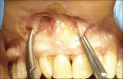

The containment of the elevator muscle of the upper lip and wing of nose was used for the treatment of patients with gummy smile. This technique had corrected esthetic alterations of smile, reducing the upper lip elevation, which results in a smaller gingival display. An upper lip lengthening as well as a reduction in the upper lip shortening when the patient smiled could be observed. The high smile line was corrected without compromising the labial harmony. This study presents an innovative and effective therapeutic option to obtain a natural and harmonious smile. The patient expressed a high degree of satisfaction.